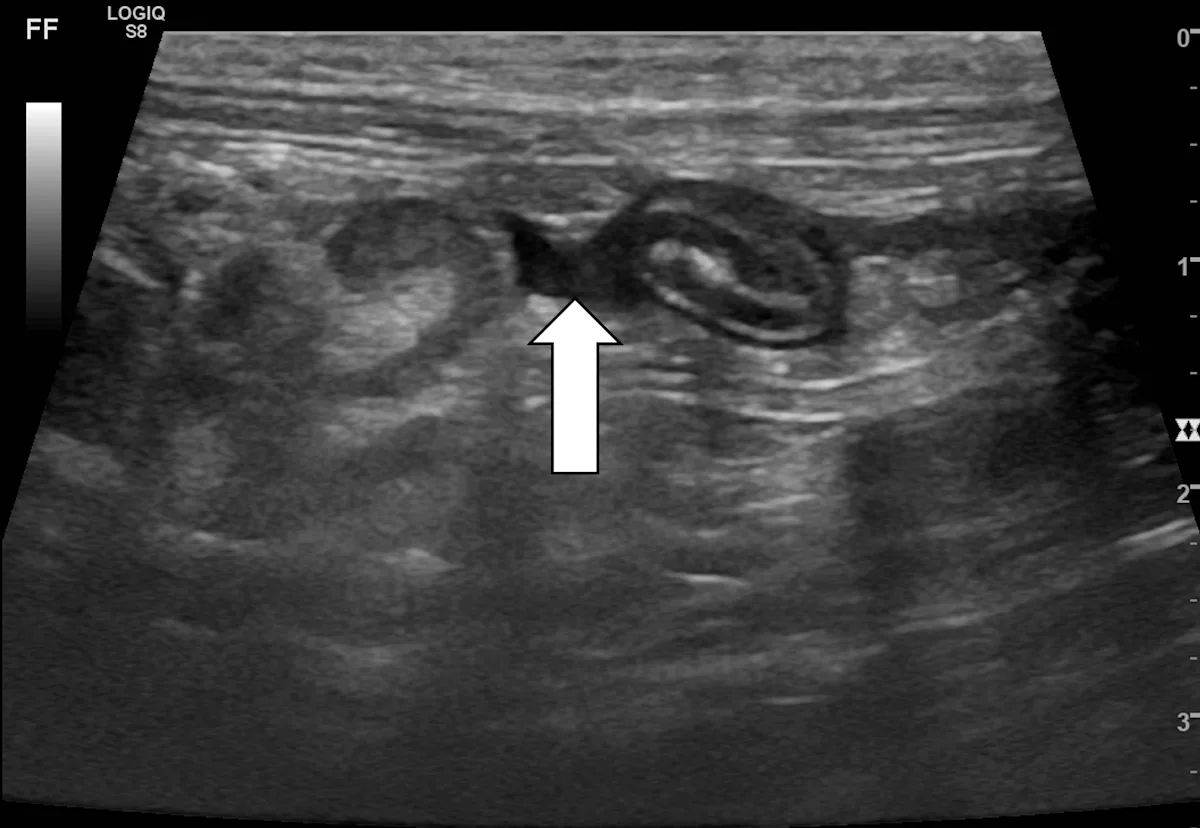

After all samples have been collected, re-evaluate the sampled regions for evidence of anechoic or echogenic acute hemorrhage (arrow).

Author Insight

A small volume of self-limiting hemorrhage is common and usually not of clinical concern. Hemorrhage can be rechecked with ultrasonography after 1 to 4 hours for signs of progression or sooner if the patient displays clinical signs of hypovolemia.